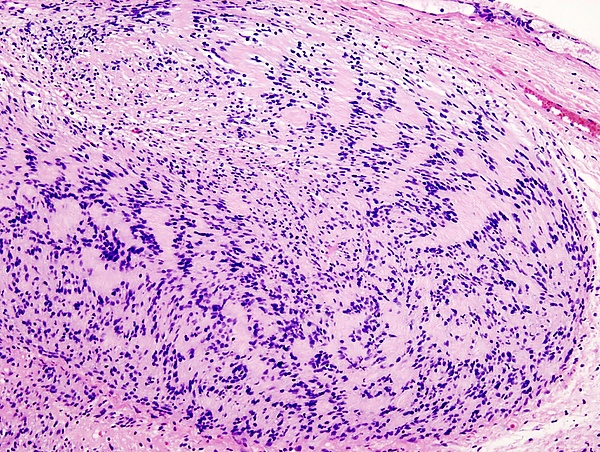

Микропрепарат опухоли окраска гематоксилин-эозин.

Невринома состоит из веретенообразных клеток с палочкоподобными ядрами. Клетки и волокна опухоли образуют «палисадные» структуры (ядерные палисады, тельца Верокаи) с участками, состоящими из волокон.

Традиционно различают два гистологических типа неврином: тип Верокаи, или тип А, и тип Антони, или тип Б. Данное разделение условно и практического значения для диагностики не имеет. Советский нейрохирург, академик АМН СССР Б. Егоров при исследовании неврином слухового нерва обнаружил, что их структурное многообразие зависит не от свойств опухолевой ткани, а от деструктивных и рубцовых процессов[1].

Микроскопическое строение опухоли на разных стадиях роста может быть различным в зависимости от интенсивности дистрофических процессов и нарушений кровообращения. Нарушения кровообращения сопровождаются скоплением гемосидерина и разрастанием фиброзной ткани. Всё это создаёт пёструю гистологическую картину[1].